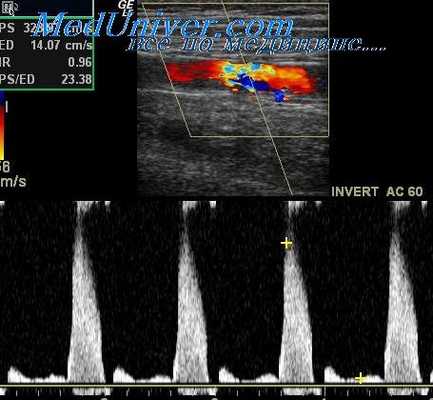

На рисунке показаны этапы проведения компрессионной пробы с целью оценки резервов коллатерального кровообращения мозга под контролем цветового дуплексного сканирования. Из рисунка видно, что компрессия ипсилатеральной (одноименной) общей сонной артерии вызывает изменение допплеровского спектра сдвига частот в СМА: тип кровотока с магистрального меняется на коллатеральный, а пиковая систолическая скорость кровотока снижается.

При подстановке значений Vps в формулу оказалось, что в момент пережатия ОСА скорость снизилась на 42%. Этот результат соответствует достаточному коллатеральному резерву мозгового кровообращения, удовлетворительной толерантности головного мозга к ишемии и стадии компенсации коллатерального кровообращения.